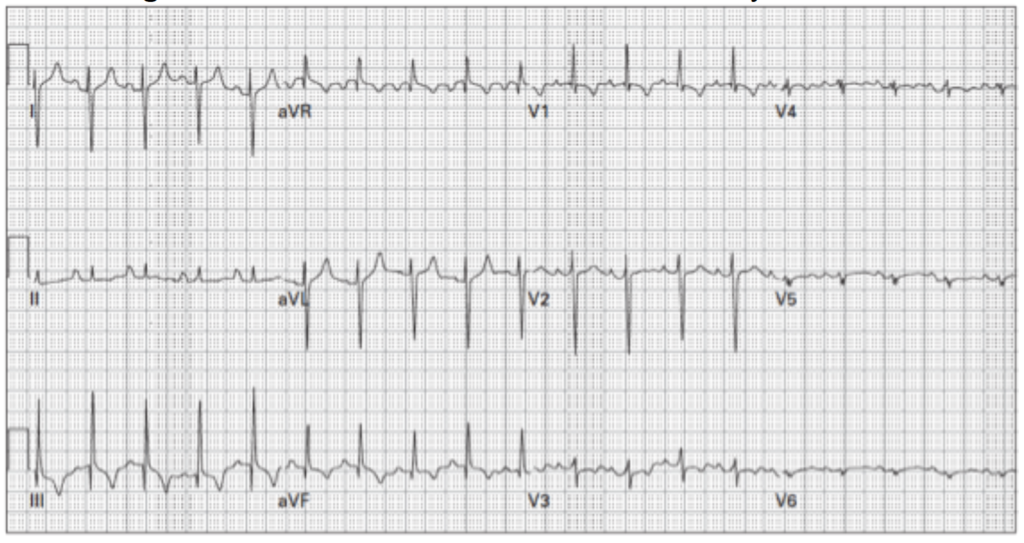

Masculino de 16 años con palpitaciones. ¿Cuál es el ritmo?